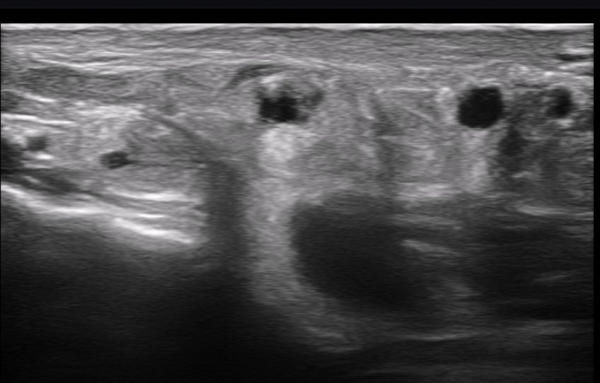

ÃÊÀ½ÆÄ ¼Ò°ß : ºñº¹½Å°æ Ⱦ´Ü¸é°Ë»ç¿¡¼­(»çÁø 1~13) ºñº¹½Å°æÀÇ Àú¿¡ÄÚ ºÎÁ¾°ú ´Üºñ°ñ°Ç³» ³¶Á¾¼º º´º¯ÀÌ °üÂûµÈ´Ù.